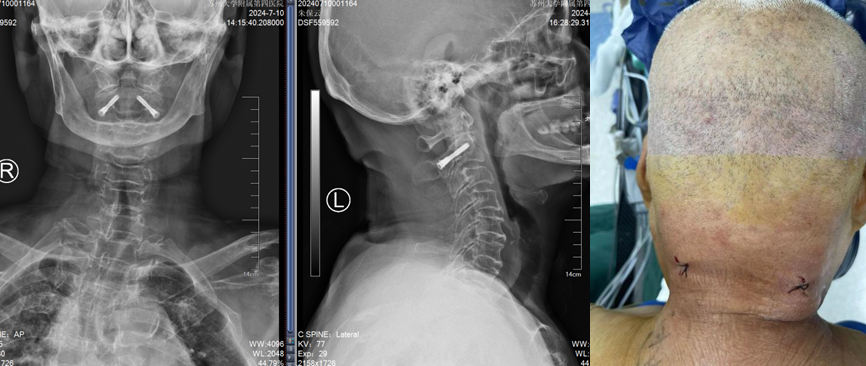

术后复查提示骨折复位,置钉精准